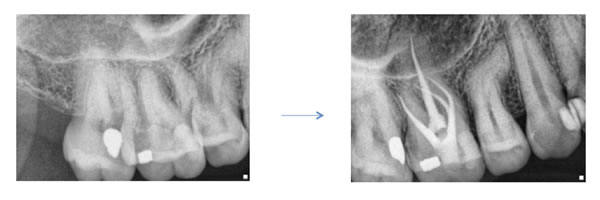

Case by Dr. Michael Sherman

Historically the dental literature reported an occurrence of this canal to be found in about 60 percent of maxillary first molars and 30 percent of maxillary second molars. With the introduction of high magnification into the field, clinicians found this canal at a rate much higher than what was reported in the past. The higher occurrence has since been verified in the endodontic literature with reports of up to 93 % in first molars and 60 % in second molars (Stropko et al, JOE 1999). In order to optimize successful treatment of maxillary molars, finding and treating the MB2 canal is essential. This canal is often difficult to find and even harder to negotiate. I have included several guidelines below that I hope will help locate and treat these canals.

Where is it?! MESIAL! A common occurrence when looking for the second mesial canal is to simply look palatal to the main mesial buccal orifice. Removal of the dentinal shelf lingual and mesial to the MB canal is important to uncover the MB2. I prefer a fine, flame diamond to extend my access to the mesial. Copious amounts of EDTA and alcohol further enhance visualization of the pulpal floor and any isthmus that can lead to the MB2. The ability to keep the pulpal floor clean and free of debris helps immensely. The better we can see the floor the easier it is to find the canal. The access should be in the shape of a rhomboid as opposed to a rectangle.